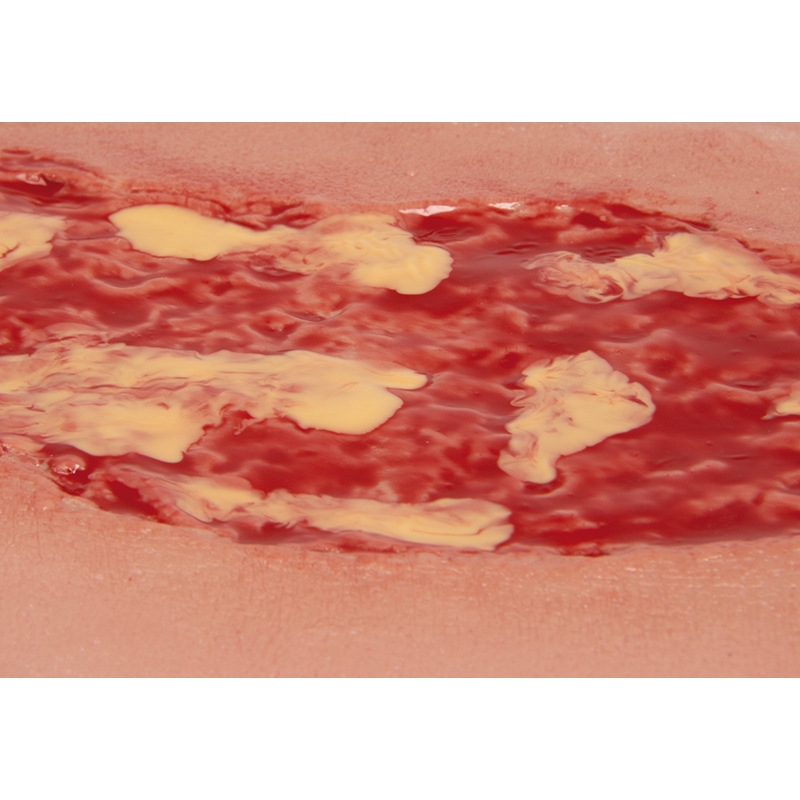

Mulaža rane venska razjeda na nogi, velika, faza eksudacije

Ta samolepilna rana predstavlja vensko razjedo na nogi, defekt snovi v tkivu spodnjega dela noge, ki je posledica kroničnega venskega popuščanja. Prikazana faza eksudacije predstavlja najpogostejšo ulkusno bolezen (60 % do 80 % vseh ulkusnih bolezni) v nezdravljenem stanju. Med čiščenjem je treba odstraniti fibrin in prekomerni ekssudat iz rane. Ta velika rana je kot nalašč za lepljenje na spodnjem delu noge in se sama prilepi. Za daljšo uporabo jo je mogoče pritrditi s posebnim kožnim lepilom. Vsi materiali, uporabljeni v tem izdelku, so dermatološko neškodljivi.